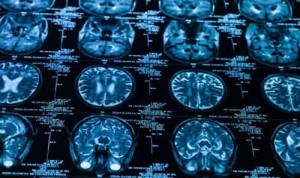

Il cervello di alcuni adolescenti subisce cambiamenti, simili agli effetti provocati da un lieve trauma cranico, dopo aver giocato a football americano anche solo una stagione e anche senza aver avuto traumi cranici.

Tramite una serie di scansioni cerebrali, effettuate prima dell’inizio della stagione e poi alla fine, i ricercatori sono stati in grado di identificare lievi modifiche nella materia bianca del cervello. La materia bianca contiene milioni di fibre nervose che fungono da “cavi” di comunicazione tra le regioni del cervello. Cosa questi cambiamenti comportano sul lungo periodo rimane ancora un mistero su cui ora gli scienziati hanno deciso di indagare a fondo.